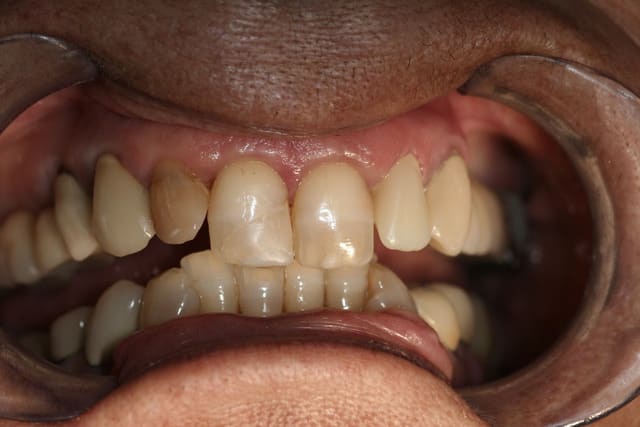

R29 uvltlt - Eugenol

R49 enunsh - Eugenol

R22 vkd0tr - Eugenol

R23 pmkimv - Eugenol

R26 gr1kkt - Eugenol

R34 w9wpow - Eugenol

Img 0052 dkvbyu - Eugenol

Leandro

28/02/2013 à 21h54

Joli travail!